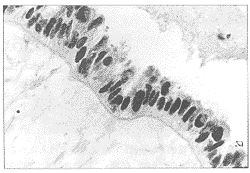

摘要 目的 :研究p16在卵巢肿瘤中的表达及意义。方法 :应用免疫组化ABC法检测133例卵巢肿瘤和12例正常卵巢组织p16的表达。结果 :卵巢肿瘤与正常卵巢组织p16表达有显著性差异。正常卵巢没有p16表达的缺失,良性、交界性、恶性组p16表达明显下降(P<0.05)。上皮性组晚期、残存癌灶≥2cm者p16表达明显低于早期、残存癌灶〈2cm者(P<0.05);p16表达与组织类型、组织分化、淋巴结转无关(P<0.05)。生存分析表明p16尚不能作为卵巢癌的独立预后因素。结论 :p16蛋白在卵巢肿瘤中存在不同程度的缺失,与卵巢癌的发生、发展有一定关系 ......